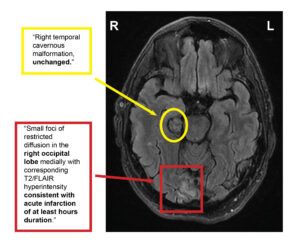

MRI Report (Figure 3)

The MRI officially confirmed a stable cavernous malformation and a new occipital lobe infarct, consistent with visual field findings. The patient was admitted to the hospital’s inpatient facility with a care team consisting of neurology, neurosurgery, and hematology.

Figure 3. Horizontal MRI section representing both the new occipital lobe infarct and the unchanged cavernous malformation. Click to enlarge